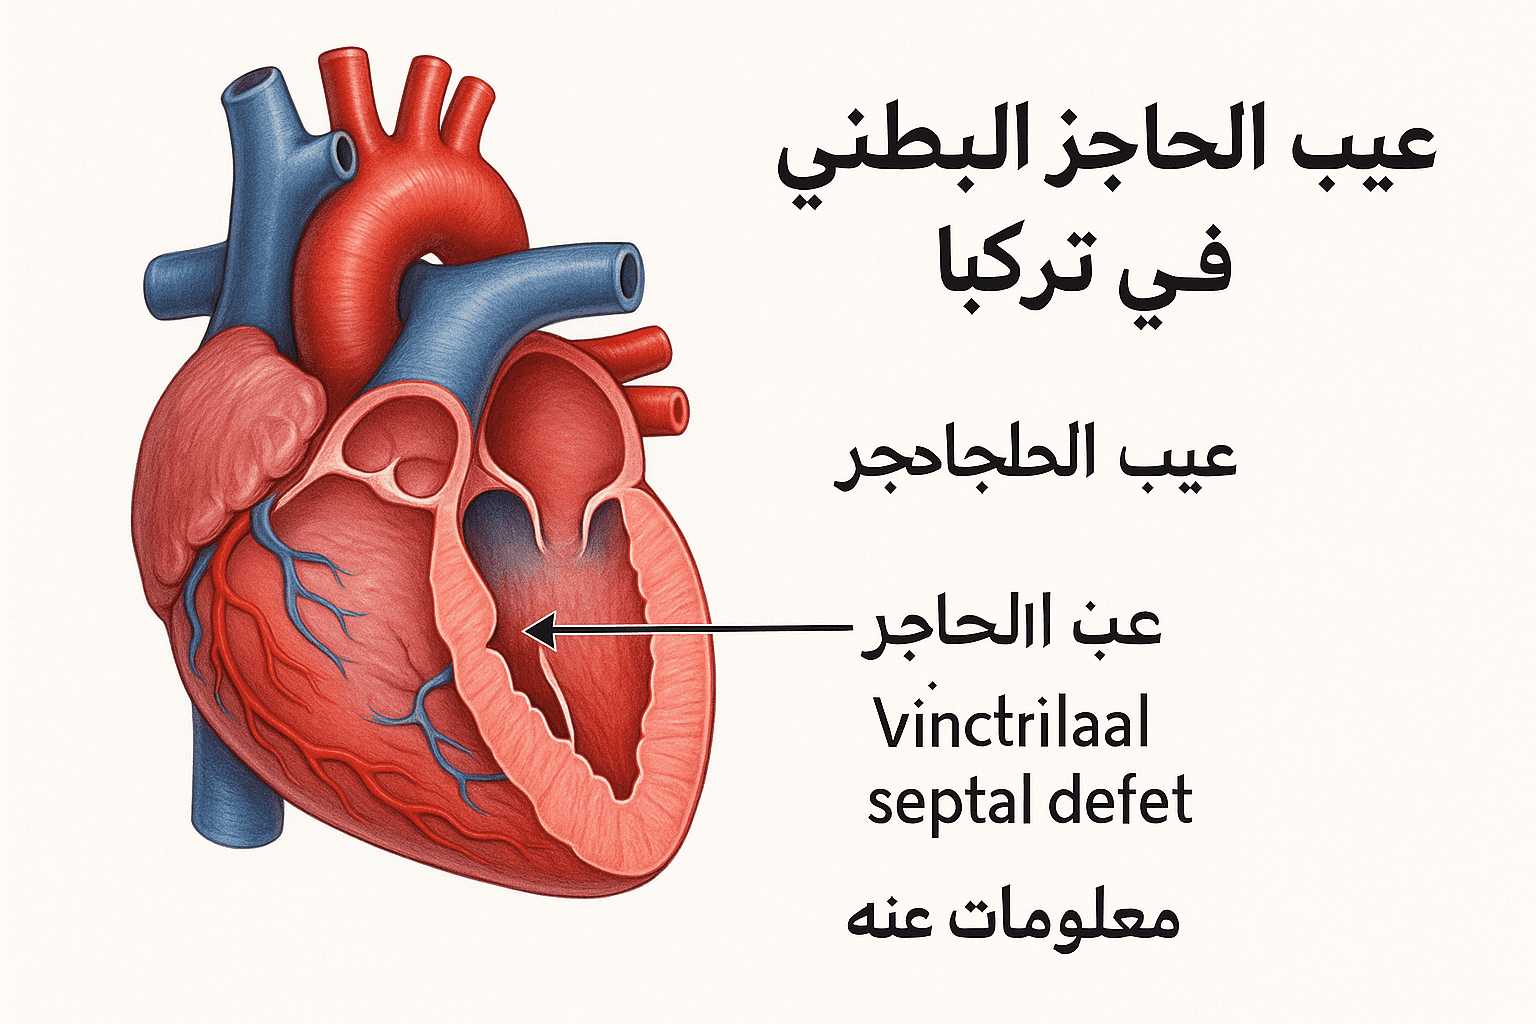

مقالات طبية من مساهمات الأطباء